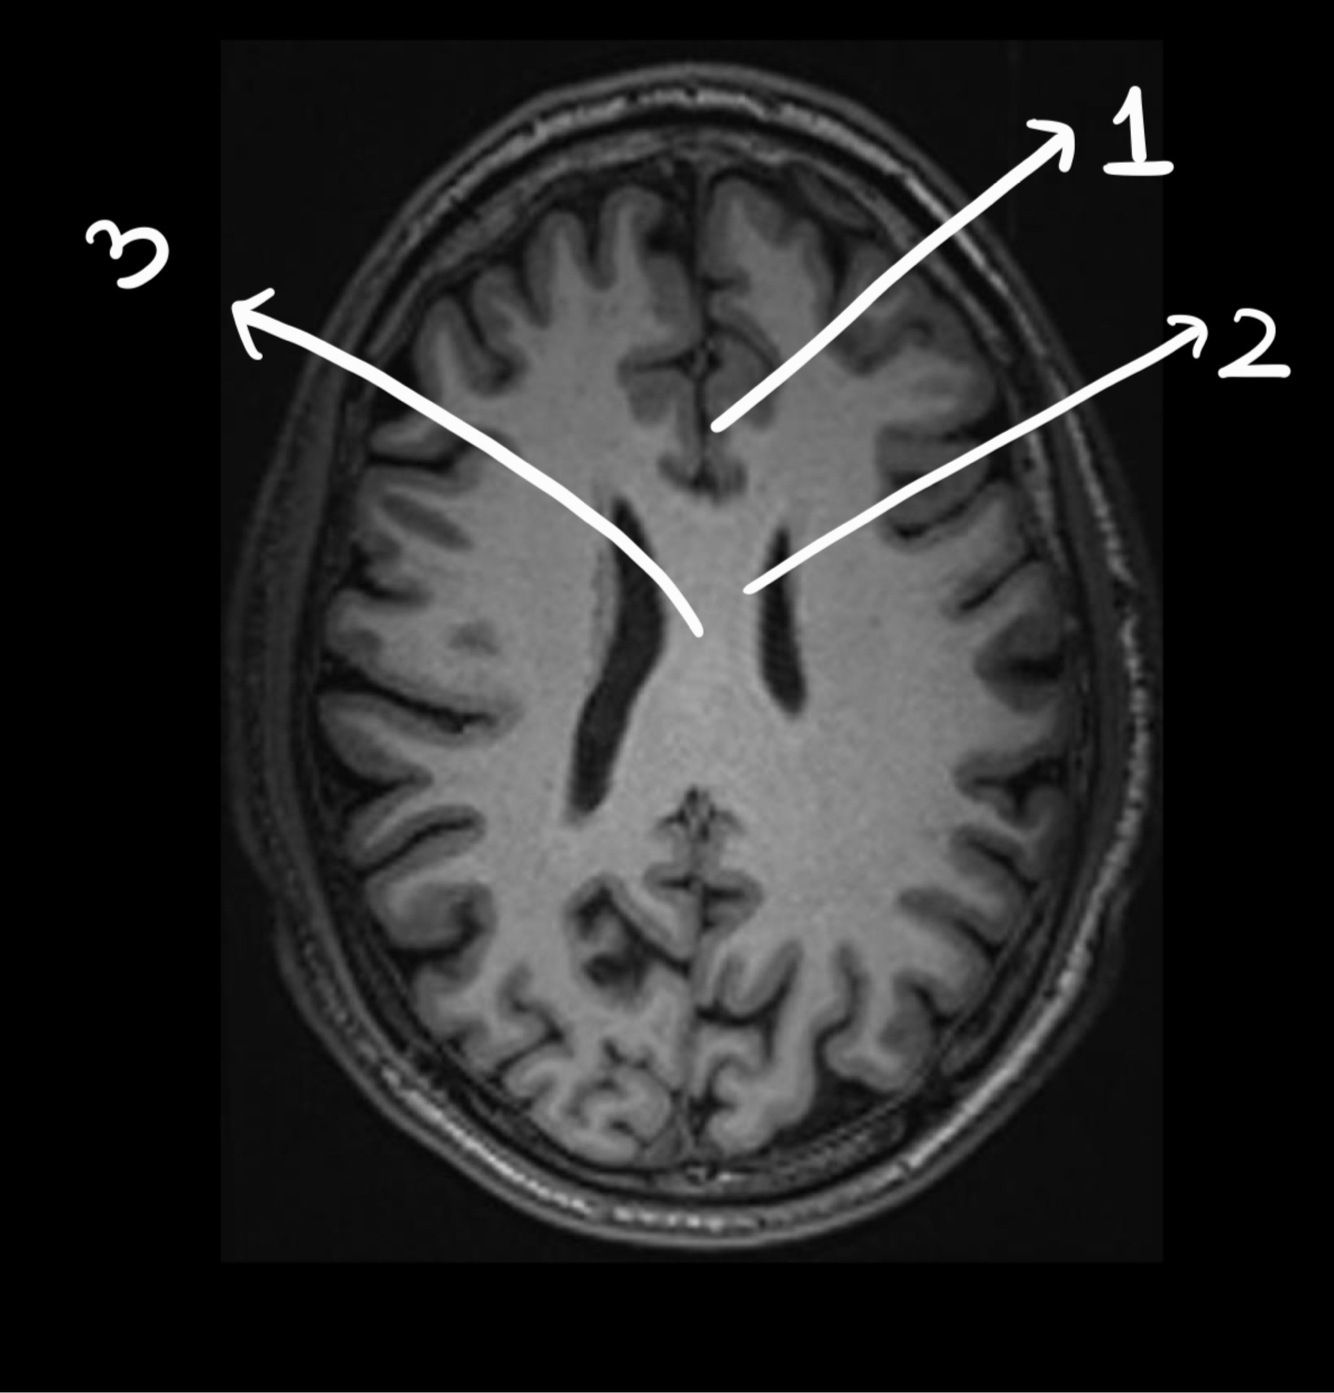

In this image we can see the…

Sylvian sulcus